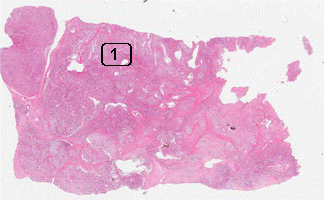

Case No.: S-003

Diagnosis: Alveolar soft part sarcoma

Anatomical Region: Soft tissue, leg

Hematoxylin & eosin

Area 1: The tumor cells are rather monotomous, with distinct cytoplasmic membrane. The tumor cell nests are separated by delicate fibrous septa.

• The histopathology of alveolar soft tissue (Area 1) tumor is rather characteristics and stay more or less the same among different tumors. The tumor is composed of nest of large polygonal, and rather monotonous cells with a moderate to large, round nuclei with prominent nuceoli. Intercellular cytoplasmic membrane is usually distinct. The tumor cells are separated by thin fibrous septa into small and large nests. Thin walled sinusoidal channels are present within these fibrous septa.